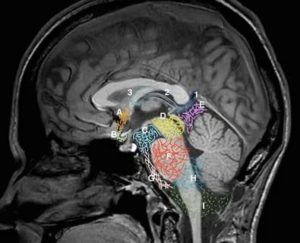

Головной мозг защищен тремя оболочками: твердой, паутинной и мягкой. Мягкая оболочка непосредственно соприкасается с мозговым веществом и отвечает за его питание. Паутинная оболочка соединена с другими оболочками мозга через соединительнотканные перегородки. В тех местах, где перегородок нет, располагаются цистерны.

Циркуляция спинномозговой жидкости происходит в четырех желудочках мозга (двух боковых, третьем и четвертом) и в субарахноидальном пространстве. Ликвор выполняет важные функции, такие как питание нейронов, удаление продуктов обмена веществ и механическая защита мозга.

Локализация кисты различна, она может находиться в ямке над турецким седлом либо около области мостомозжечкового угла.